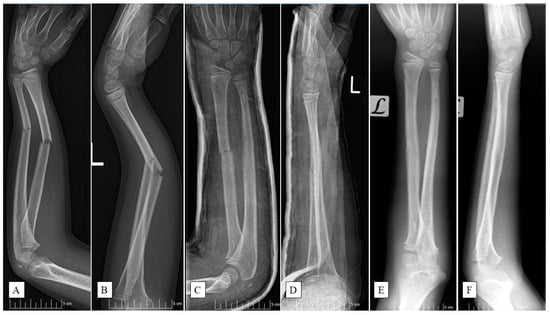

PLGA implants (Activa IM-Nail™, Bioretec Ltd., Tampere, Finland) function by maintaining their mechanical strength throughout the critical period of bone healing (Figure 1).

These polymers degrade through hydrolysis, breaking down into lactic acid and glycolic acid monomers [23,24]. Subsequently, the monomers are metabolized via the citric acid cycle, producing water and carbon dioxide as end products. This process lowers the local pH, creating an acidic environment around the implant which facilitates its gradual resorption. Complete degradation of PLGA typically occurs within 9–12 months, making it a reliable material for temporary internal fixation in pediatric patients [25]. Additionally, the implants feature a tricalcium phosphate (β-TCP) marker for precise fluoroscopic placement (Figure 1C–F).

Figure 1. An 11-year-old boy fell while playing football and had a deformed left (L) arm. Preoperative anteroposterior (AP) (A) and lateral (B) radiographic views of the forearm exposed subperiosteal fractures of both ulna and radius. X-rays post-surgery ((C)—AP, (D)—lateral aspects) show the successful insertion of PLGA implants, confirmed by the radiopaque markers. Six-month control images ((E)—AP, (F)—lateral views) revealed completely healed fractures with good axial alignment.